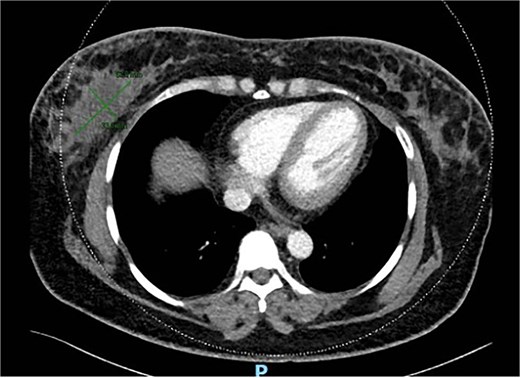

She underwent excision biopsy of the 80 mm right breast siliconoma in Aug 2021. Histology showed 80 mm invasive mammary carcinoma with apocrine component. GATA 3 positive, CK7 positive. Estrogen receptor (ER) and progesterone receptor (PR) negative and cerB2 positive. Margins were involved anteriorly, superiorly and posteriorly. Staging computed tomography (CT) scan showed multiple nodules scattered in both breasts and post-surgical seroma including a lobulated and enhancing soft tissue in retro-areolar region (Fig. 7). No metastasis noted.

MRI breast showed seroma from excision biopsy and delayed enhancement in the anterior aspect of the collection that may represent residual disease (Fig. 8). She underwent breast conserving surgery to obtain clear margins, and sentinel node biopsy. Wide excision histology showed residual 13 mm invasive carcinoma with clear margins and one lymph node positive on sentinel node biopsy. She subsequently underwent axillary clearance and completion nipple-sparing mastectomy and reconstruction with free deep inferior epigastric perforator (DIEP) flap (Fig. 9). Histology revealed no residual carcinoma and further nodal metastasis. She underwent adjuvant chemotherapy, targeted therapy and radiotherapy. She has remained well 3 years after her surgery and continues to be screened for cancer annually with a MRI for her contralateral breast.